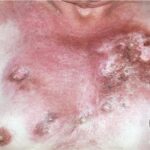

- Disseminated blastomycosis usually begins with pulmonary infection followed by cutaneous, osseous, genitourinary, or CNS involvement.

- Skin lesions are the most common manifestation of extrapulmonary disease. Cutaneous lesions favor exposed areas and enlarge over many weeks, from pimples that are minimally tender to well-circumscribed verrucous or ulcerative lesions, often with little inflammation. Verrucous lesions demonstrate raised irregular borders with crusting and purulent drainage, whereas ulcerative lesions are characterized by sharp and heaped-up borders with centrally located granulation tissue and exudate.